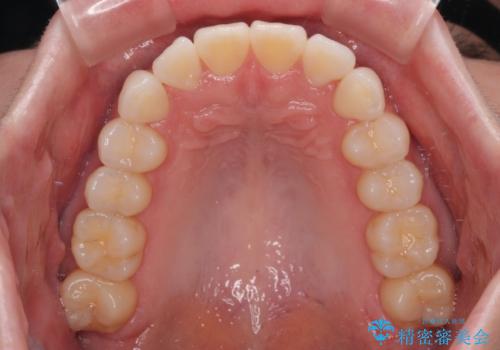

- 上下前歯の叢生を気にして来院された患者様です。

軽度な叢生であり、安価で短期間の治療を規模されていたため、インビザライン・モデレートを用いて矯正治療を行うこととしました。